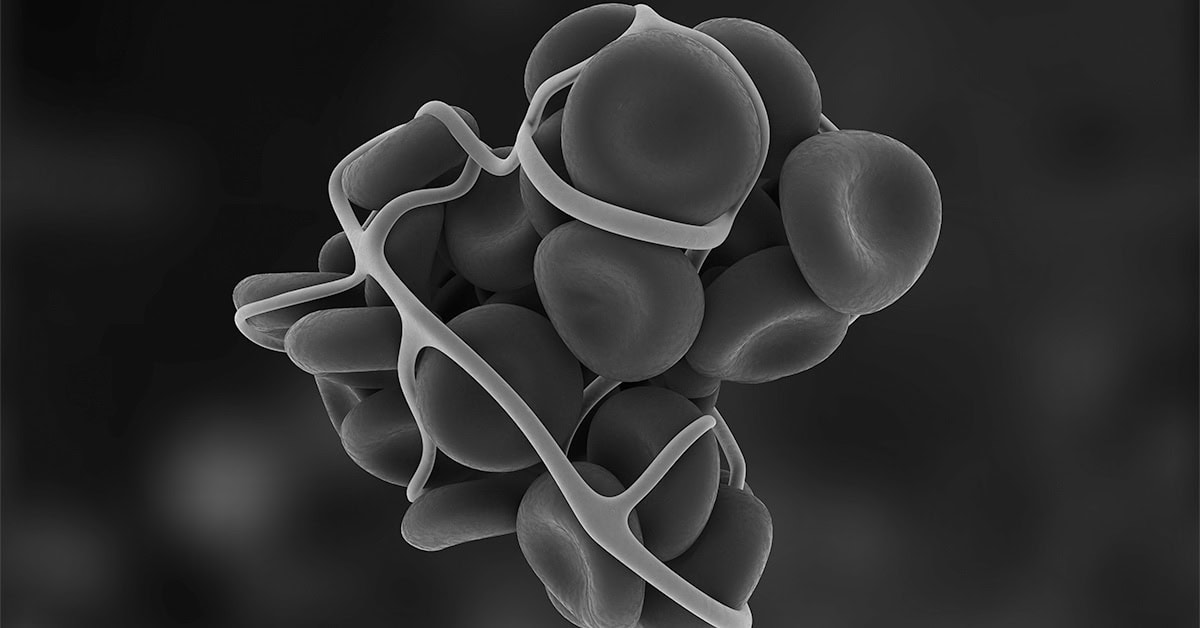

• Figure S3. Splanchnic Vein Thrombosis In Patient 4. Venous Phase CT ...